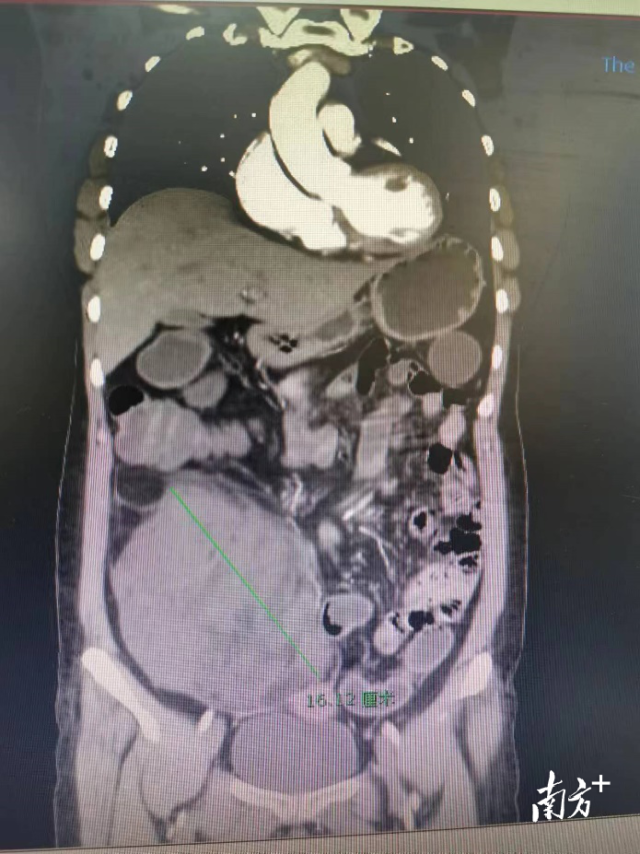

检查显示肿瘤的位置。

张姨再也不敢怠慢,前往暨南大学附属第一医院找到了胃肠外科杨景哥主任医师诊治。在经过了详细的检查后,杨景哥指出,让张姨肚子慢慢长大的并不是“脂肪”,而是一个皮球大小的腹膜后肿瘤!而且肿瘤直径长达16cm,短短半年时间,肿瘤快速增大进展,巨大的肿瘤几乎占据了张姨半个腹腔,并且对周围邻近的脏器产生了明显的压迫。

手术团队认为,张姨的肿瘤范围较大,位于腹膜后由右肾水平延伸至盆腔,包膜完整,采用腹腔镜微创手术优势较大。通过肚子上小小的几个孔,以最小的创伤,可以兼顾上下腹操作。